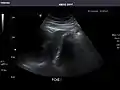

Abdominal Ultrasound (Full Exam)

STRUCTURED REPORT

(Technique: Transabdominal ultrasonography; Device: Toshiba Aplio XG)

Liver: Diffusely homogeneous and normal in echogenicity. No focal mass or contour nodularity. No intrahepatic biliary ductal dilatation.

Portal Vein: Patent main portal vein.

Gallbladder: No stones, wall thickening, or pericholecystic fluid.

Common Bile Duct: Nondilated measuring 1.3 mm at the level of the porta hepatis.

Pancreas: Visualized portions unremarkable.

Spleen: Normal in size.

Kidneys: Right and left kidneys measure 11.5 cm and 12 cm in length respectively. No hydronephrosis. Small left lower pole kidney cyst.

Ascites: None.

Aorta: Visualized portions normal in caliber, 16 x 15 mm.

IVC: Normal.

IMPRESSION:

Normal abdominal ultrasound.